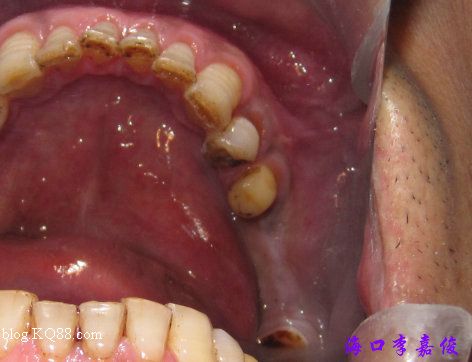

下牙牙齦菲薄

37種植窩成形后植入4.8X10mm植體

術(shù)后